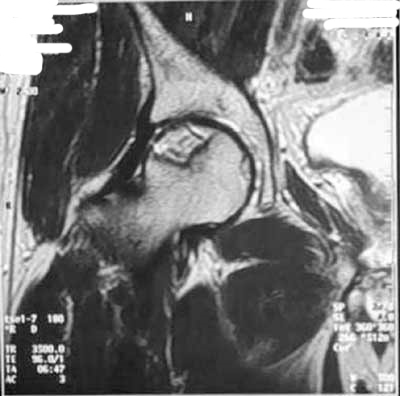

Tout oriente vers une épiphysiololyse de la hanche :

– la douleur chronique, localisée au genou avec toutefois un examen clinique du genou normal

– la position vicieuse du membre inférieur en rotation externe

– la limitation de la mobilité de la hanche, principalement en abduction et rotation interne

– le patient est un jeune homme en période pubertaire, avec un surpoids